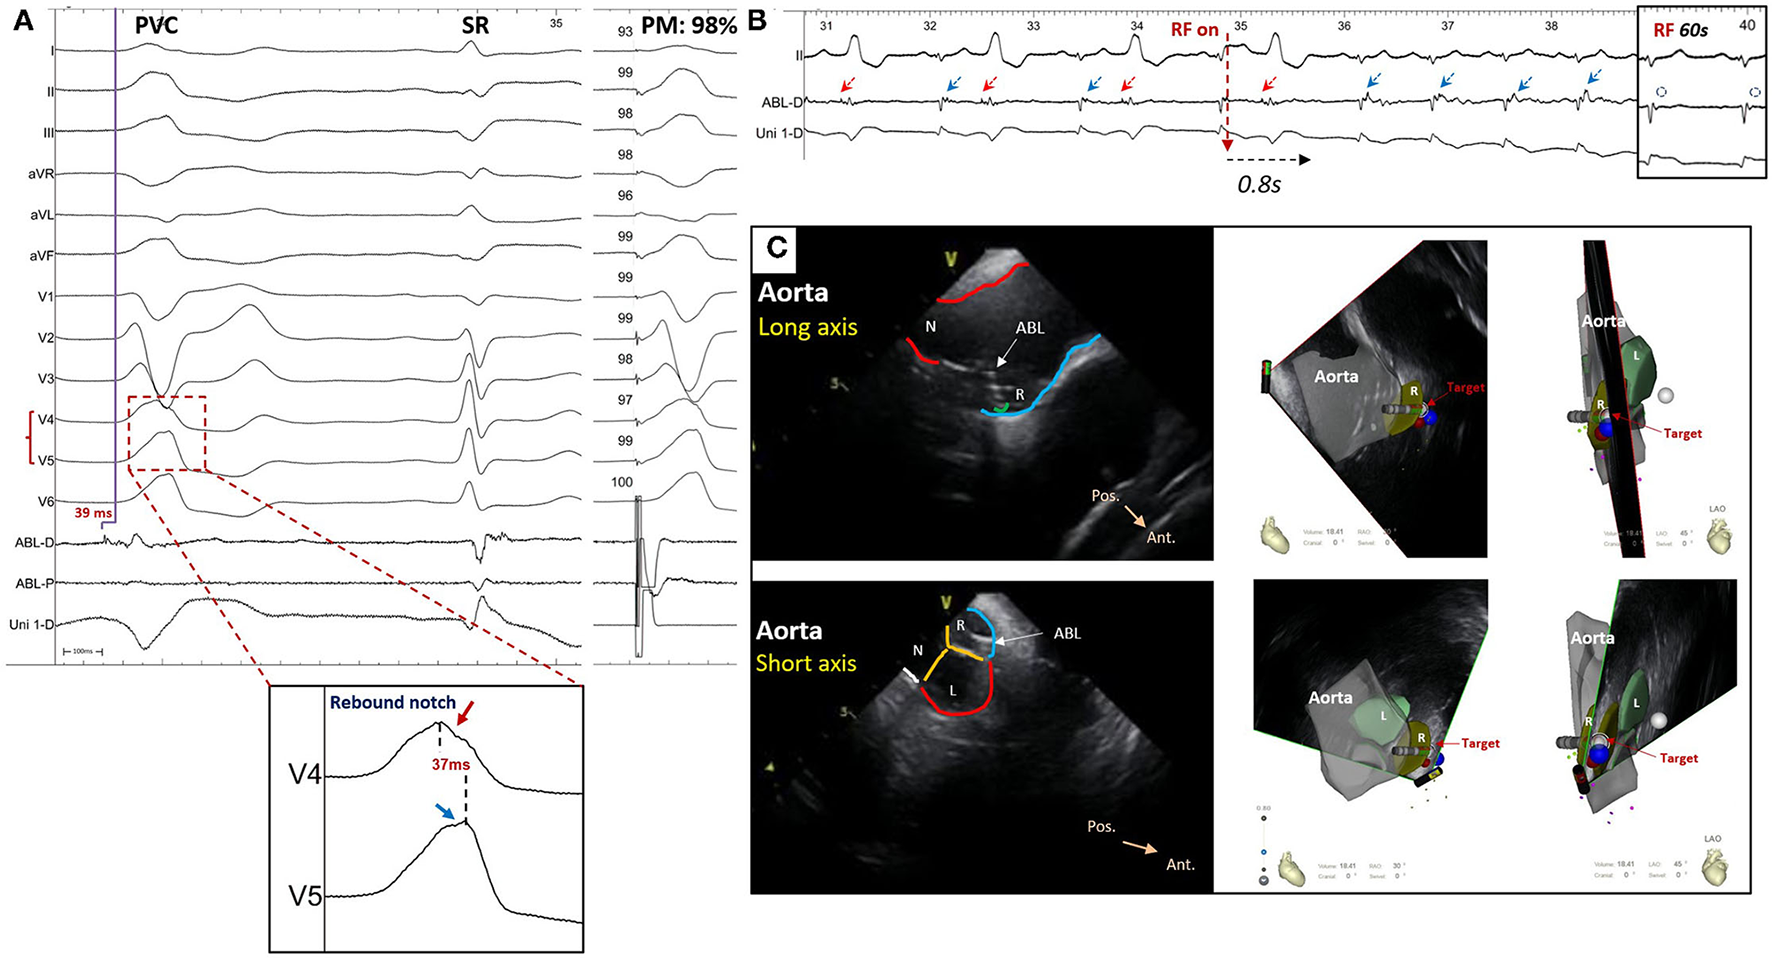

Diagnostic Value of Precordial Rebound Notch

A rebound notch in V3-V4 or V4-V5 (Figure 5) was observed in 91% (10/11) of VAs from the right-anterior ASV, while it was less likely to appear in other subregions (6/40, 15%). Among VAs ablated in the right and left ASV, a rebound notch in V3-V4 or V4-V5 had a sensitivity of 90.9%, a specificity of 85.0%, a positive predictive value (PPV) of 62.5%, and a negative predictive value (NPV) of 97.1% to predict VAs ablated in the right-anterior ASV (Figure 2). Meanwhile, the peak R-wave deflection interval difference between V4-V3 and V5-V4 during VAs was significant between the right-anterior/lateral ASV and other subregions (41 ± 19 vs. 13 ± 17, p < 0.01); a cutoff value of 32 ms (area under the curve, 0.82; CI, 0.67–0.98; p < 0.01) predicted an ablated target in the right-anterior/lateral ASV with a sensitivity of 83.0% and a specificity of 87.0% (Figure 3).

A patient who suffered from premature ventricular contraction (PVC) with left bundle branch block morphology and inferior axis deviation ablated in the right-anterior ASV. (A) The ECG of PVC showed a rebound notch on leads V4-V5; the final target revealed a reversal potential (compared with sinus rhythm) that preceded the onset of QRS for 39 ms during PVC and the pace mapping showed a similarity of 98%. (B) The ventricular bigeminy rhythm disappeared immediately after radiofrequency (RF) initiation and the late potential (blue arrow) during sinus rhythm was eliminated after 60 s of RF. (C) The ablated target was located at the right-anterior ASV through intracardiac echocardiography. ABL-D/P, distal or proximal bipolar electrogram; Uni-D, distal unipolar electrogram; SR, sinus rhythm; PM, pace mapping; ABL, ablation catheter; ASV, aortic sinus of Valsalva; N, non-coronary ASV; L, left ASV; R, right ASV; Pos., posterior; Ant., anterior.

A rebound notch in V2-V3 during VAs was more common in the left-lateral ASV (6/12; 50 vs. 5%, p < 0.05). Among VAs ablated in the right and left ASV, a rebound notch in V2-V3 had a sensitivity of 50.0%, a specificity of 94.9%, a PPV of 75.0%, and a NPV of 86.0% to predict VAs ablated in the left-lateral ASV (Figure 2). Meanwhile, the peak R-wave deflection interval difference between V3 and V2 during VAs seemed greater in the left-lateral ASV, but showed no significance when compared with other subregions (19 ± 16 vs. 12 ± 11, p > 0.05). A cutoff value of 31 ms had a sensitivity of 33.3% and a specificity of 92.3% to predict VAs ablated in the left-lateral ASV.